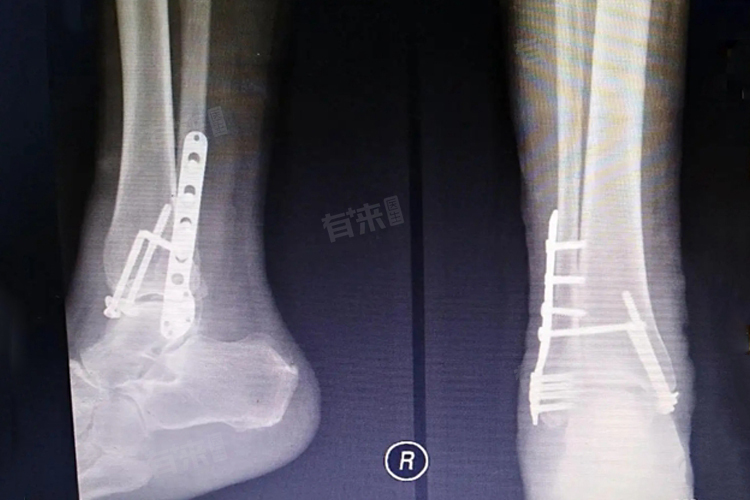

- 医生要根据骨折的类型和形态,选择合适规格的钢钉。钢钉的长度、直径和形状都要精准匹配骨折部位,以实现良好的固定效果。在植入过程中,需要将钢钉准确地穿过骨折断端,使其紧密贴合,这要求医生有高超的操作技巧。

- 对于简单的骨折,如手指骨折,打钢钉手术相对简单,手术时间较短,风险也较低。但对于复杂的骨折,如骨盆骨折、脊柱骨折等,打钢钉手术难度大,风险高,术后恢复也更复杂。